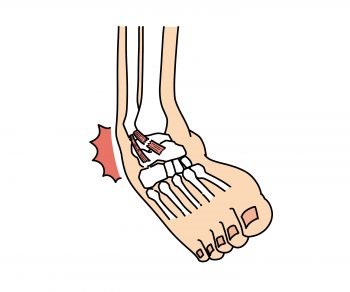

■ 捻挫は「伸びただけ」ではない

足首の捻挫で来院された方に、

よく聞く言葉があります。

「一応腫れてるけど、歩けるから大丈夫かと…」

確かに歩けることもあります。

でも、靭帯は確実にダメージを受けています。

痛みが我慢できるレベルでも、

内部では炎症が起きていることが多い。

そのまま動き続けると、

腫れが長引いたり、

クセになりやすくなります。

捻挫を繰り返す方には、

共通して“最初の処置が甘かった”ケースが多いです。